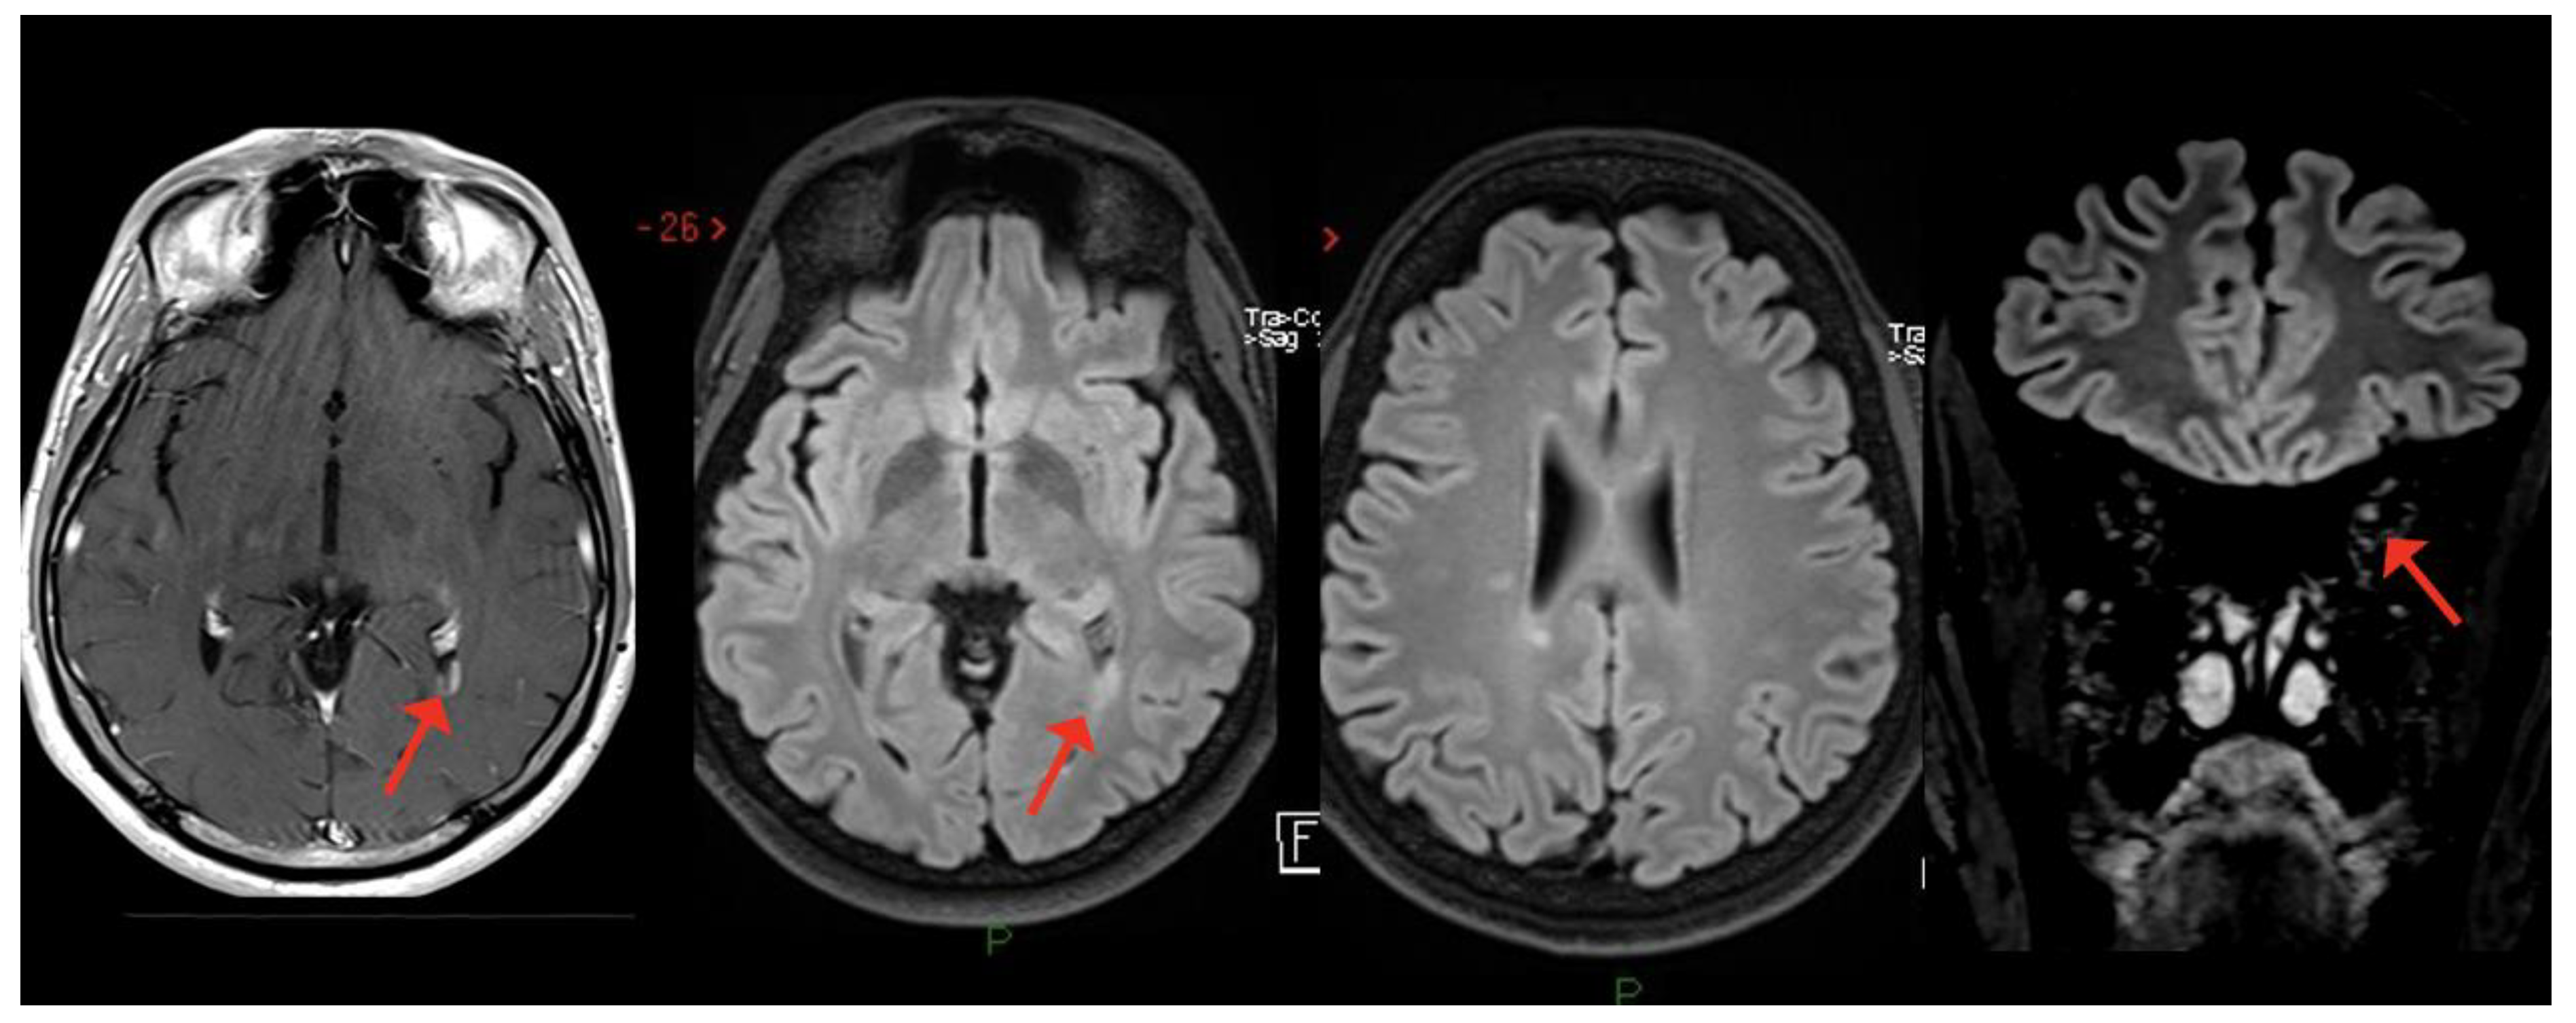

2. MS Onset after SARS-CoV-2 Exposure

3. MS Relapses after COVID-19 Infection

| Case 1 | 2 weeks | BS (dyplopia) | - | + | + | - | +/+ |

| Moore et al. [52] | 2 weeks | BS (dyplopia) | BS, ST | + | + | NA | +/+ |

| Pignolo et al. [55] 1st case | 8 weeks | BS (facial palsy) | - | + | + | - | +/+ |

| Ismail et al. [76]. | 8 weeks | Cerebellum | - | + | + | - | -/- |

| Case 2 | 2 weeks | ON | - SC | + | - | - | +/+ |

| $ Case 3 | 2 weeks | ON | - | + | + | - | +/+ |

| Palao et al. [56] | 2 weeks | ON | ST | + | + | - | +/+ |

| Sarwar et al. [57] | 3 weeks | ON and unilateral motor deficit | ST | + | NA | NA | -/- |

| Case 4 | 4 weeks | SC | SC | + | + | + | +/+ |

| Fragoso et al. [58] | 6 months | SC | ST, SC | + | + | - | +/+ |

| Avila et al. [59] * | 2–6 weeks | 40% SC 40% ON 20% BS | NA | NA | + | 80% - 20% + | NA/+ |

| Feizi et al. [60] | 1 week | SC | SC | + | + | NA | +/+ |

| MS RELAPSE | |||||||

| Pignolo et al. [55] 2nd case | 2 months | Uncertain (unilateral motor symptoms) | ST | + | + | - | NA |

| $ Case 5 | 3 weeks | Cerebellum (trunk/gait ataxia, dysmetria) | NA | NA | NA | + | NA |

| Finsterer [61] | 2 weeks | SC (sensory symptoms both inferior limbs and trunk level) | SC | + | + | - | NA |